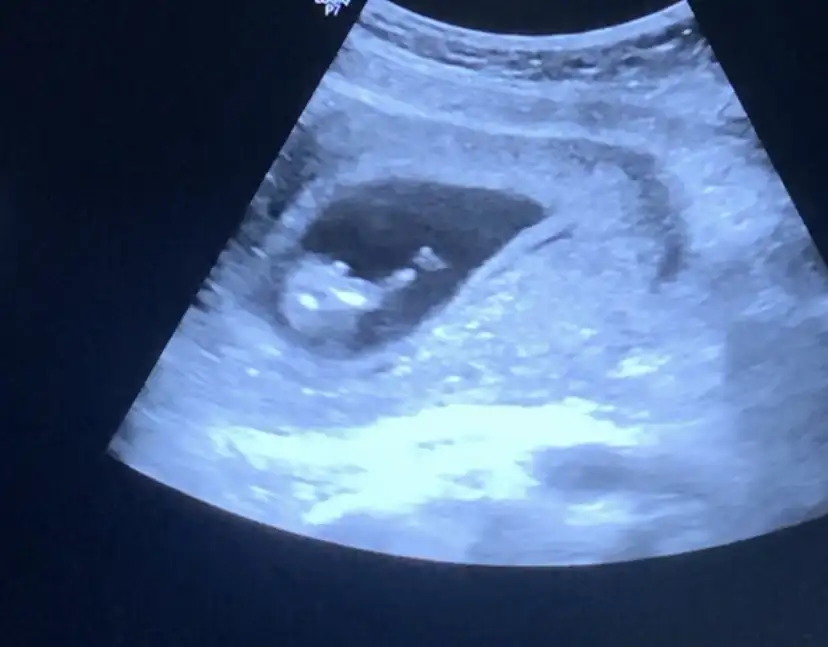

Hayırlısı olsun canım, kız bebekleri ayrı bir severim çok sevindim gerçektenGünaydınlar herkese2 hafta önce kendi doktoruma kontrole gitmiştim 2li test için ama kendisi bir sonraki kontrolü 5 hafta sonraya verdiği için dün dayanamadim başka doktora gittim 1 haftadır hiçbir belirtim yoktu panik oldum çok şükür her şey yolunda çok çok hareketli yaramaz bir KIZiniz olacak dedi doktor kendi doktorum da kız demişti zaten artık tam emin olduk Rheaa